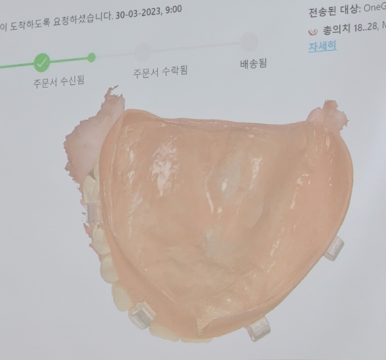

거기다 실제 임프레션도 해볼 수 있도록

러버와 임플란트 모델까지 준비해서

마음껏 연습할 수 있도록 했답니다!

대학교 치위생과에서도 특성화 사업을 진행하면서

임플란트 뻔강, 보철임프레션 강의 요청이 들어와서

진행도 했었는데요! 아무래도 실습이라는 특성때문에 인원을 나눠서 진행했는데 만족도가 아주 높았답니다!

아래는 실제 학생들이 인상채득한 거에요!

잘했쥬?